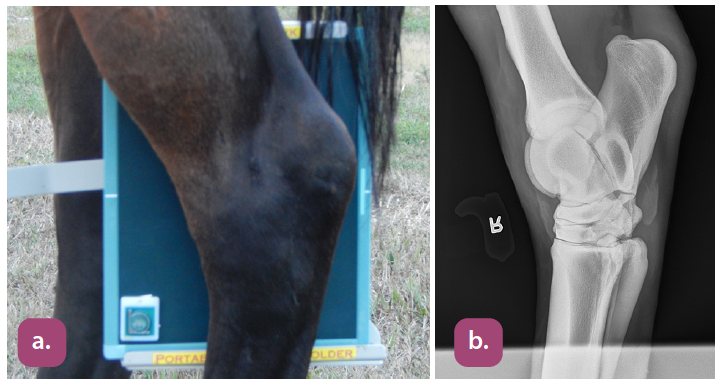

flexed lateral fetlock projection

dorsopalmar fetlock projection

flexed lateral carpus projection

extended lateral carpus projection

dorsopalmar carpus projection